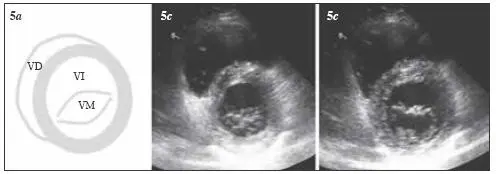

Fig 35 Visión del plano paraesternal de eje corto transversal a nivel de la - фото 31

Fig. 3.5 Visión del plano paraesternal de eje corto (transversal) a nivel de la válvula mitral (basal). 5a) Visión esquemática; 5b) sístole; 5c) diástole. VD = ventrículo derecho; VI = ventrículo izquierdo; VM = válvula mitral.